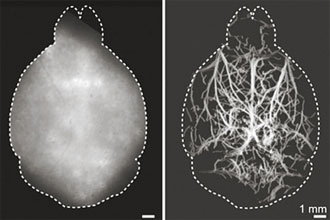

研究人员首先在模仿人体平均大脑组织特性的组织合成模型中测试了这项技术,证明他们可以在光学不透明的组织中获得最深达4毫米的显微分辨率图像。然后,他们在活小鼠身上测试了这项技术。他们给活小鼠静脉注射了荧光微滴,追踪这些流动的荧光微滴可以重建小鼠大脑深部微血管的高分辨率图。观察发现,借助DOLI技术可以完全无创地观察到脑微血管以及血流的速度和方向。

研究人员表示,这种方法消除了背景光散射,并可在头皮和头骨完好无损的情况下进行。他们还观察到相机记录的斑点大小与微滴在大脑中的深度有很大的关系,这使大脑深度分辨成像成为可能。